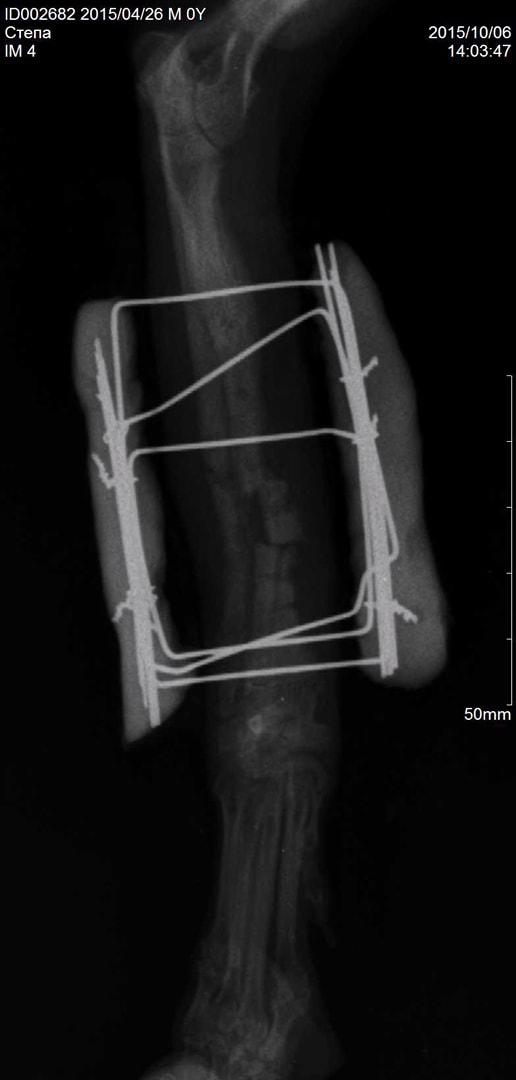

Медицинские снимки: Пластина в левом предплечье